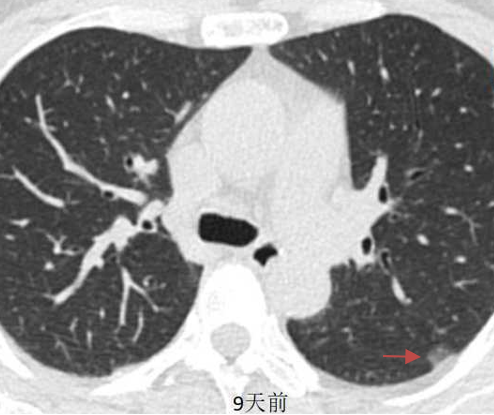

另外一个患者治疗后,随访3个月结节完全消失。